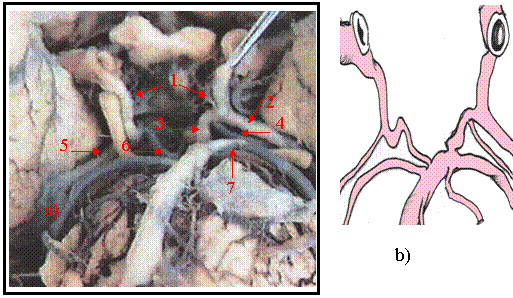

Cazul 3 [figura 9.3 a) si b) ]

Figura 9.3 a) vasele sectorului posterior al poligonului lui Willis b) prezentare schematica

1 - arterele comunicante posterioare. 2 - ramura laterala a comunicantei posterioare stangi. 3 - ramura mediala a comunicantei posterioare stangi. 4 - un segment P-2 din ramura mediala a comunicantei posterioare stangi. 5 - segmentul P-2 al cerebralei posterioare drepte. 6 - segmentul P-1 al cerebralei posterioare drepte. 7 - un segment P-2 al cerebralei posterioare stangi.

In sectorul posterior al poligonului lui Willis la acest caz arterele comunicante posterioare se continua cu segmentul P-2 al cerebralelor posterioare. Segmentul P-1 al cerebralei posterioare drepte apare ca o anastomoza a trunchiului arterial bazilar cu artera comunicanta posterioara dreapta. Segmentul P1 al cerebralei posterioare stangi se anastomozeaza cu o ramura mediala a comunicantei posterioare stangi dupa care se continua cu un segment P-2. Din ramura mediala a comunicantei posterioare se detaseaza o artera ce se orienteaza spre lateral si posterior, un alt segment P-2, de calibru mai mic decat al segmentelor P-2 ce continua cerebrala posterioara si P-2 ce continua comunicanta posterioara. Aceste trei segmente P-2 au traiect aproape paralel incat pot fi considerate ca trei artere cerebrale posterioare. .